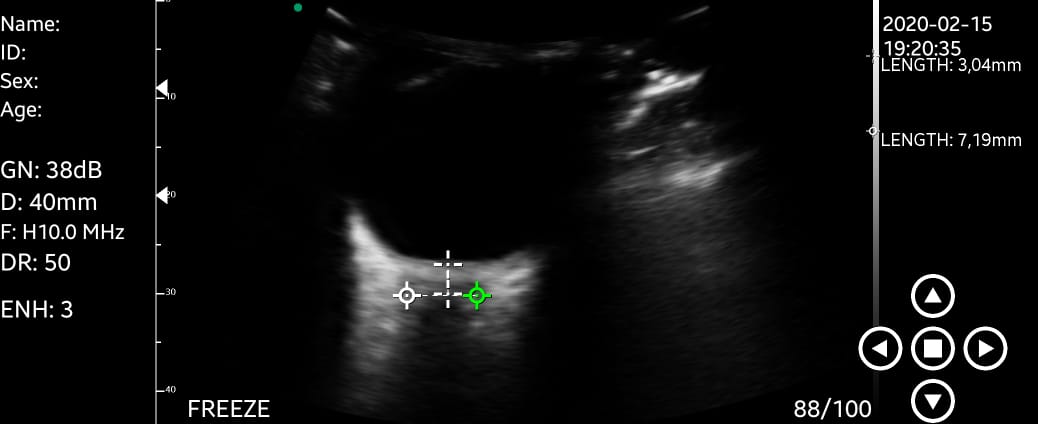

Esse estudo pode ser feito beira leito, com um transdutor de alta frequência, tendo como exemplo o probe linear. A estrutura a ser visualizada é a entrada do nervo optico no globo ocular, com sua respectiva bainha. Devemos então obter uma imagem que mostre a distensão máxima da bainha, com mensuração de seu diâmetro de 3mm posterior ao globo. Feito isso, traçamos uma linha reta usando o diâmetro transversal máximo da bainha, atravessando o ponto final dos 3mm determinados anteriormente.

Na imagem abaixo podemos ver um paciente com sinais de hipertensão intracraniana, com ultrassom de nervo optico mostrando um diâmetro da bainha de 7,19mm, compatível com o quadro clinico.